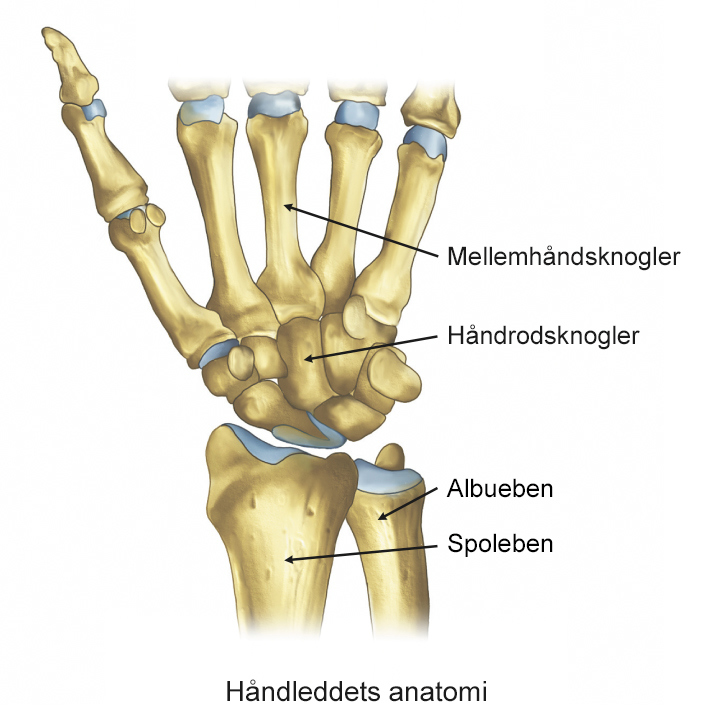

I underarmen findes to knogler, som strækker sig fra albueleddet til håndleddet:

- Spolebenet, som ligger på tommelfingersiden

- Albuebenet, som ligger på lillefingersiden

Brud på spolebenet er det mest almindelige og sker ofte ved fald på strakt arm. Det kan medføre forskellige fejlstillinger, som giver smerter og nedsat bevægelighed og påvirke håndens funktion i hverdagen.